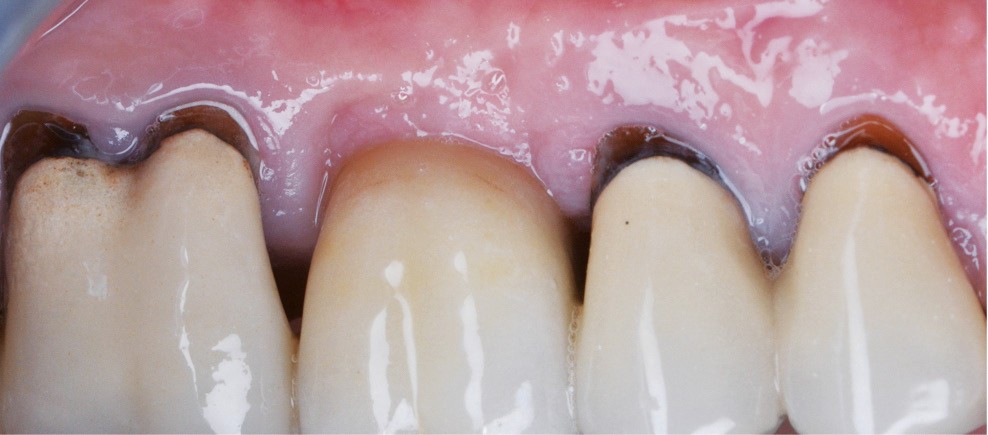

Zuchelli et coll. [1] définissent quatre causes à l’origine des récessions gingivales à la suite d’une déhiscence osseuse : les causes traumatiques (fig. 1) par le brossage, le surcontour prothétique, les piercings ; les causes bactériennes (fig. 2) liées à une inflammation marginale ; les causes virales par le virus de l’herpès simple ; et les origines mixtes, à savoir traumatiques et bactériennes (fig. 3). Le diagnostic de récession liée à la plaque dentaire dépend de la présence de dépôts tartriques et/ou d’inflammation des tissus environnant les zones exposées. En présence d’une origine mixte, la récession est d’abord initiée par un brossage traumatisant, rendant la surface radiculaire hypersensible ou irrégulière, ayant une répercussion négative sur le brossage et l’accessibilité à l’hygiène.